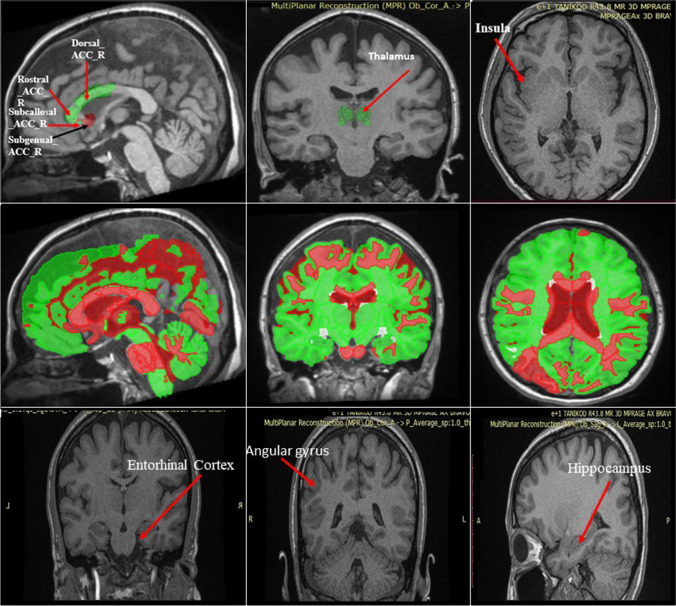

Voxel-Based Morphometry and MRICloud Analysis

In order to analyze the volumetric changes in the brain regions associated with the senses of smell and taste, 3-dimensional (3D) cranial MR images of the participants were obtained. The volumes of the olfactory cortex, insula, hippocampus, amygdala, orbitofrontal cortex, angular gyrus, and thalamus were analyzed using the VBM8 toolbox working in SPM8 in MATLAB 7.12 (R2011a) (the Wellcome Trust Centre for Neuroimaging, UK). T1 images were normalized, segmented, and smoothed respectively, and standard routines and default parameters of the VBM8 toolbox were applied. For determining the volumes of the entorhinal cortex, orbitofrontal gyrus, and anterior cingulate cortex, hdr/img files were uploaded to the MRICloud website (https://braingps.mricloud.org/), and automated segmentation and volumetric analysis were performed (Figs. 1 and 2). OB volume was measured separately by an experienced neuroradiologist and an experienced neuroanatomist separately using ImageJ Segmentation Editor (Fig. 3). Each observer made the measurement twice blindly, and the mean of all measurements was recorded.

Fig. 1.

Representative images showing the segmentation of magnetic resonance images of volunteers in the MRICloud system

Fig. 2.

3D representation of structures whose volume is measured in the MRICloud system